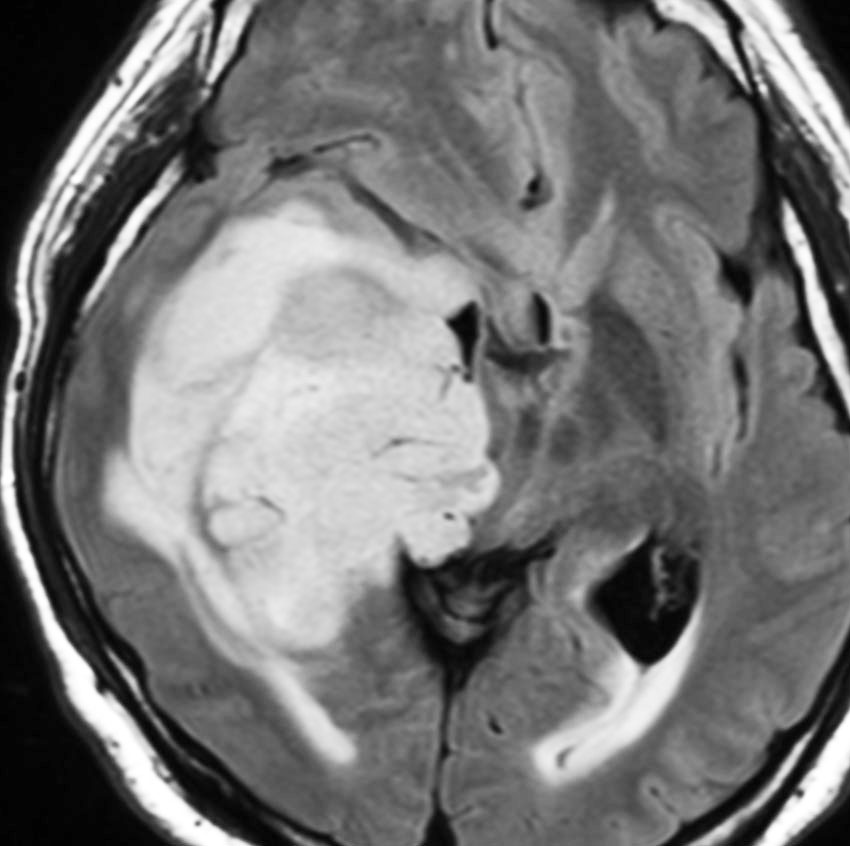

左がガドリニウム増強像で,手術ではこの部分が取れれば全摘出といわれるのですが,実際は右側のフレア画像で白っぽく見える所には腫瘍が滲み込んでいます。この部分を全て摘出してはじめて,画像上の全摘出といいます。全摘出は無理でしょう

• しかし,ほんとうの腫瘍の広がりは,T2強調あるいはFLAIR(フレア)という画像で,白く滲むように写る部分すべてです

• 手術でガドリニウム増強される部分が全部取れると,お医者さんは全摘出できたといいますが,それは間違いです

• FLAIR画像で白く見える部分が全て取れてはじめて,画像上での全摘出と言えます

• それでもなお,隠れた腫瘍細胞は周囲に滲み込んで残っています